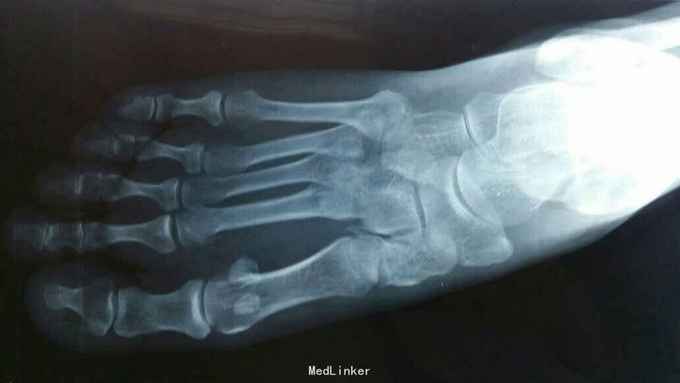

主诉:右足外伤后肿痛,活动受限11天。 现病史:患者于2015年11月10日摔伤右足,当即肿痛,活动受限,急去当地医院拍片及入院行石膏固定保守治疗,效果不佳,为求进一步治疗来诊我院,经门诊阅片及查体后以“右足多发骨折,脱位,韧带损伤”为诊断收入院。

查体:右足略肿胀,畸形明显,足背压痛广泛阳性,可触及骨擦音及骨察感,活动受限,末梢各趾活动自如,足背动脉清。 辅助检查:大致正常。

诊断:右足多发骨折伴跖跗关节脱位,韧带损伤 治疗:患者入院后,完善检查,于2015年11月25日行手术治疗,现切口愈合良好。